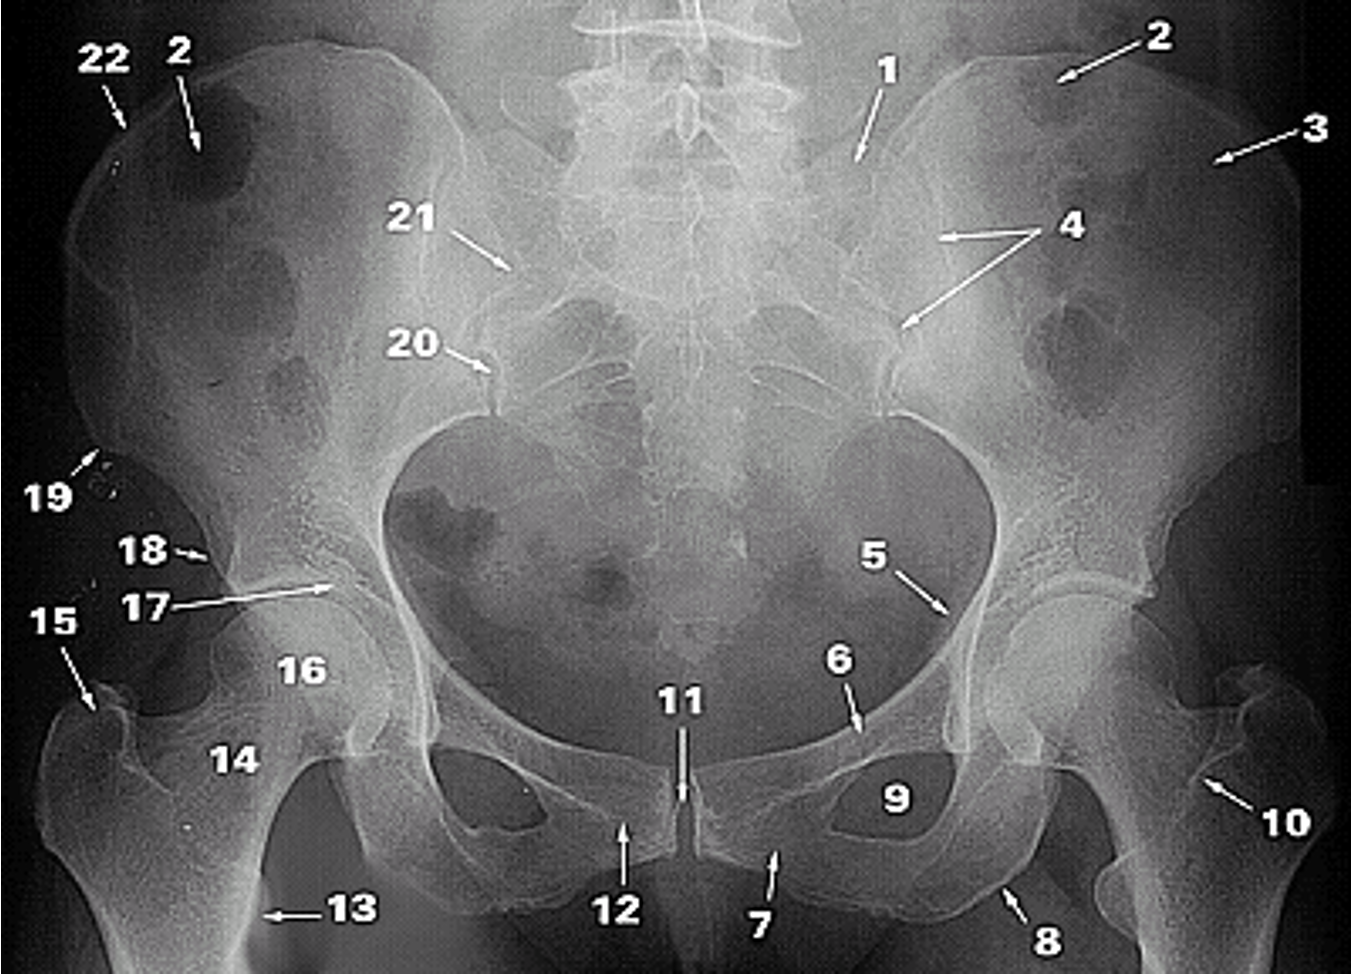

<p>1.</p>

1.

Lateral Part of the Sacrum

<p>2.</p>

2.

Gas in colon

<p>3.</p>

3.

Ilium

<p>4.</p>

4.

Sacroiliac Joint

<p>5.</p>

5.

Ischial Spine

<p>6.</p>

6.

Superior Ramus of Pubis

<p>7.</p>

7.

Inferior Ramus of Pubis

<p>8.</p>

8.

Ischial Tuberosity

<p>9.</p>

9.

Obturator Foramen

<p>10.</p>

10.

Intertrochanteric Crest

<p>11.</p>

11.

Pubic Symphysis

<p>12.</p>

12.

Pubic Tubercle

<p>13.</p>

13.

Lesser Trochanter

<p>14.</p>

14.

Neck of Femur

<p>15.</p>

15.

Greater Trochanter

<p>16.</p>

16.

Head of Femur

<p>17.</p>

17.

Acetabular Fossa

<p>18.</p>

18.

Anterior Inferior Iliac Spine

<p>19.</p>

19.

Anterior Superior Iliac Spine

<p>20.</p>

20.

Posterior Inferior Iliac Spine

<p>21.</p>

21.

Posterior Superior Iliac Spine

<p>22.</p>

22.

Iliac Crest